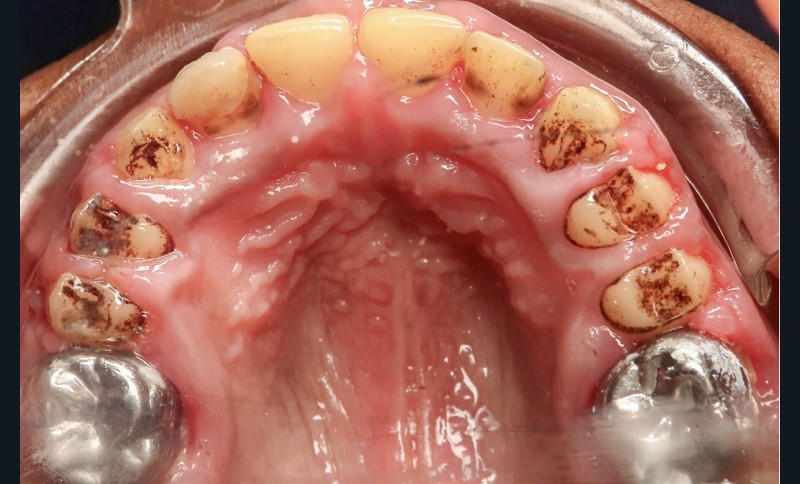

L’examen exobuccal met en évidence un profil dolichofacial et des anomalies majeures de structure dentaire (fig. 1). L’examen intrabuccal (fig. 2) montre :

- une hypoplasie sévère de l’émail ;

- une hyperplasie gingivale inflammatoire ;

- des hauteurs coronaires très réduites ;

- des couronnes pédodontiques sur les premières molaires permanentes ;

- des caries sur 17 et 27 ;

- des défauts d’éruption des quatre deuxièmes molaires permanentes ;

- de nombreux diastèmes et l’absence des dents de sagesse.